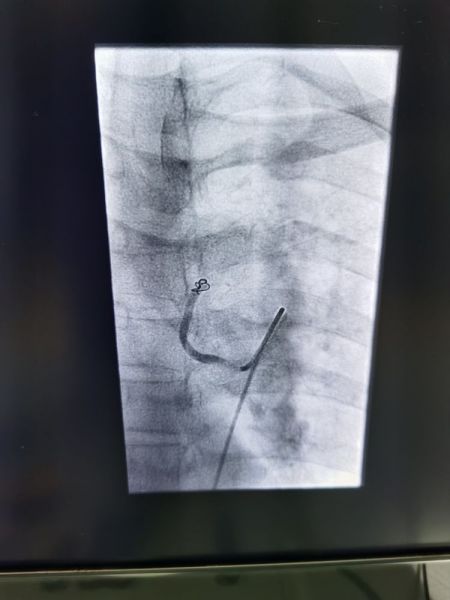

我院CTA发现两只粗大支气管动脉。